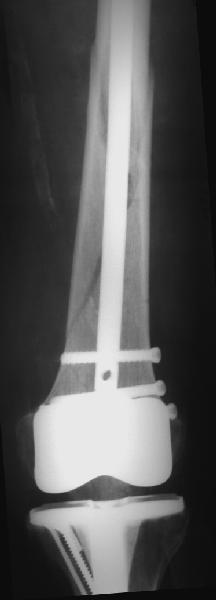

Представляю вам один из наших недавних случаев выполнения малоинвазивного остеосинтеза бедренной кости обычной пластиной 95 градусов. Длина восстановлена с помощью дистрактора (по сути это основная и б(о)льшая часть репозиции). Произведено два небольших доступа, проведена спица направитель. Рентген-контроль для подтверждения достаточной длины/оси (ЭОП использовался в другой операционной). Создание туннеля обратной стороной фиксатора. Поворот фиксатора, введение клинка по спице. Фиксация проксимального и дистального концов пластины.

Получилось очень симпатично, поздравляю и восхищаюсь мастерством.

Хотя закрытый остеосинтез блокированным гвоздем выглядит технически проще, особенно при диафизарных переломах. Не говоря о биомеханических преимуществах внутрикостного имплантата, еще меньшей инвазивности, возможности динамизации при проблемах со сращением... Стоимость гвоздей и пластин сопоставимая, на рынке есть масса отечественных предложений.

В приложении - недавний перипротезный перелом.